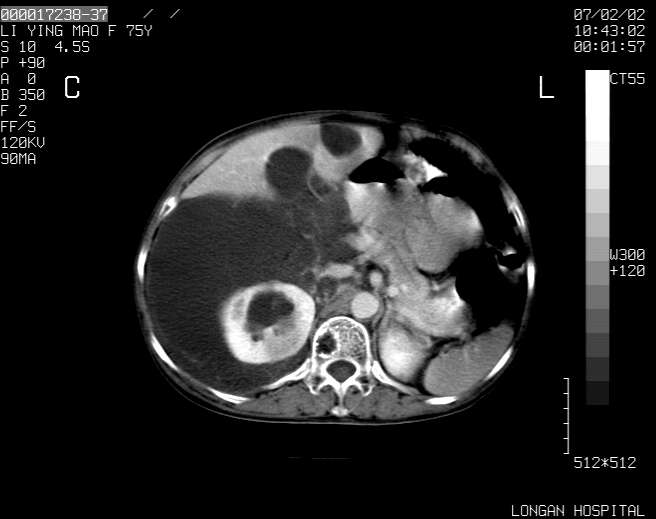

以下是引用dyqct在2007-2-10 8:53:00的发言:[br]考虑:1、肝脏多发囊肿[br] 2、左肾囊肿,右肾多发结石并积水。[br] 3、右胸少量积液。[br] 4、右肾周包裹性积液或淋巴管瘤(有见缝就钻的征象、薄隔、小结节状钙化)?[br] 5、腰椎动脉瘤样骨囊肿?[br] [br] [br]